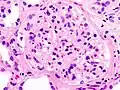

Гистопатологическая картина диабетического гломерулосклероза с нефротическим синдромом.

Гистопатологическая картина диабетического гломерулосклероза с нефротическим синдромом. Другой почечный клубочек.